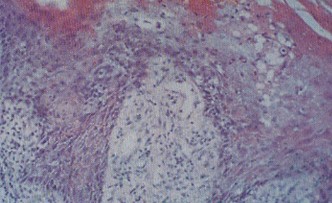

男性尖銳濕疣的發病機制發病部位肉眼可見散在疣狀或乳頭狀損害。組織病理檢查可見表皮角化不全,棘層高度肥厚,表皮突增厚延長,呈乳頭樣增生,表皮與真皮之間界限清楚。其真皮水腫,毛細血管擴張,周圍有較致密的慢性炎癥細胞浸潤。